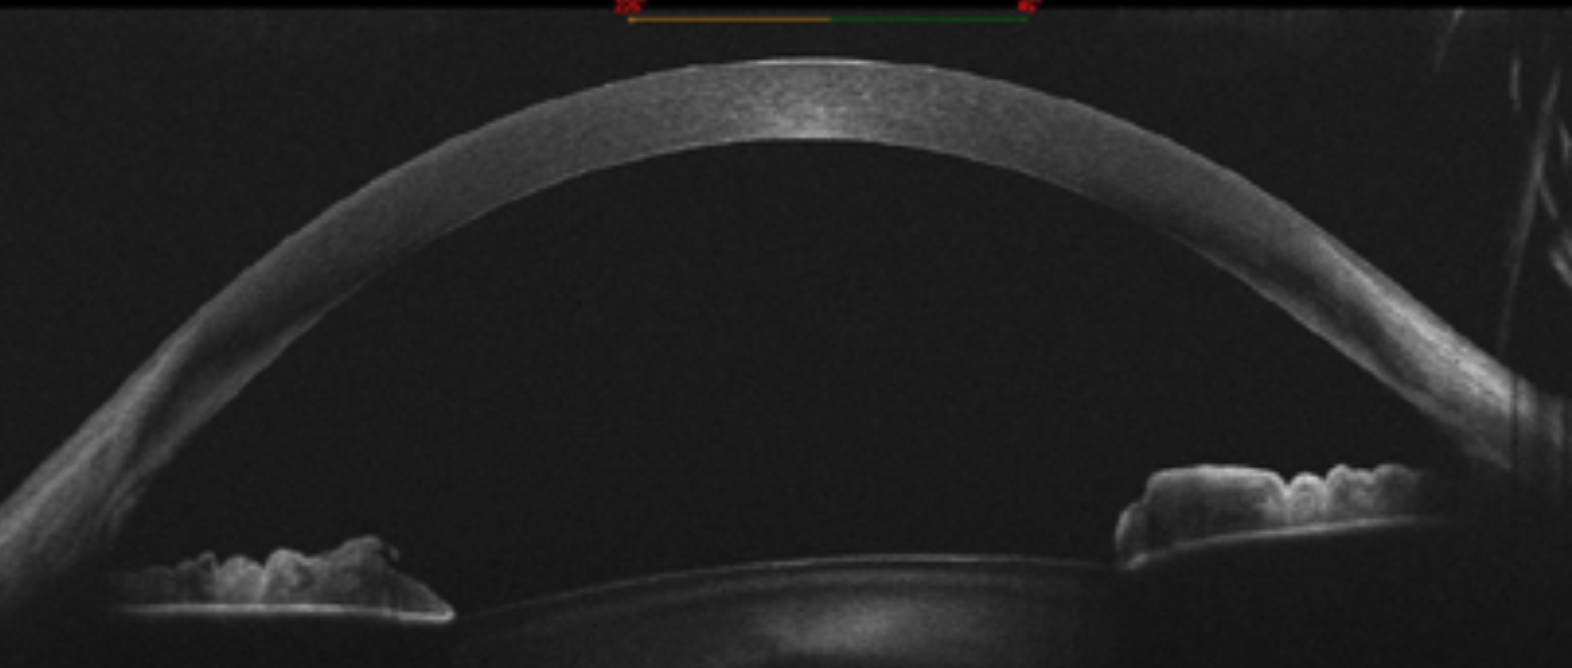

• OCT de segmento anterior, tomografia corneal.

• OCT de angulo, tomografia de angulo iridocorneal.

El queratocono es una enfermedad del colágeno que genera una córnea en forma de “cono”, generalmente comienza en la adolescencia, causa un astigmatismo elevado e irregular causado por la deformación de la córnea.

La visión borrosa y la distorsión de las imágenes son sus síntomas, puede notarse mayormente en la visión nocturna, pudiendo estar asociados otros síntomas: fotofobia, fatiga ocular e irritación de los ojos, necesidad de frotarse los ojos constantemente, cambios de anteojos frecuentes, intolerancia a lentes de contacto entre otros.

La progresión de la enfermedad suele ser mayor en un ojo y suele haber asociación familiar. Diagnosticada y tratada a tiempo puedes detenerse, el diagnóstico se realiza en la consulta con el oftalmólogo y mediante la realización de un estudio complementario denominado topografía.

Existen diferentes alternativas de tratamiento según el grado evolutivo, en los primeros estadios (tempranos) puede detenerse la progresión del queratocono mediante una cirugía denominada CROSS LINKING CORNEAL, se realiza utilizando una vitamina activada utilizando un láser rayos UV, esta cirugía suele asociarse con la implantación de segmentos intracorneales o “ANILLOS” para regularizar la superficie corneal y mejorar la corrección de astigmatismo.